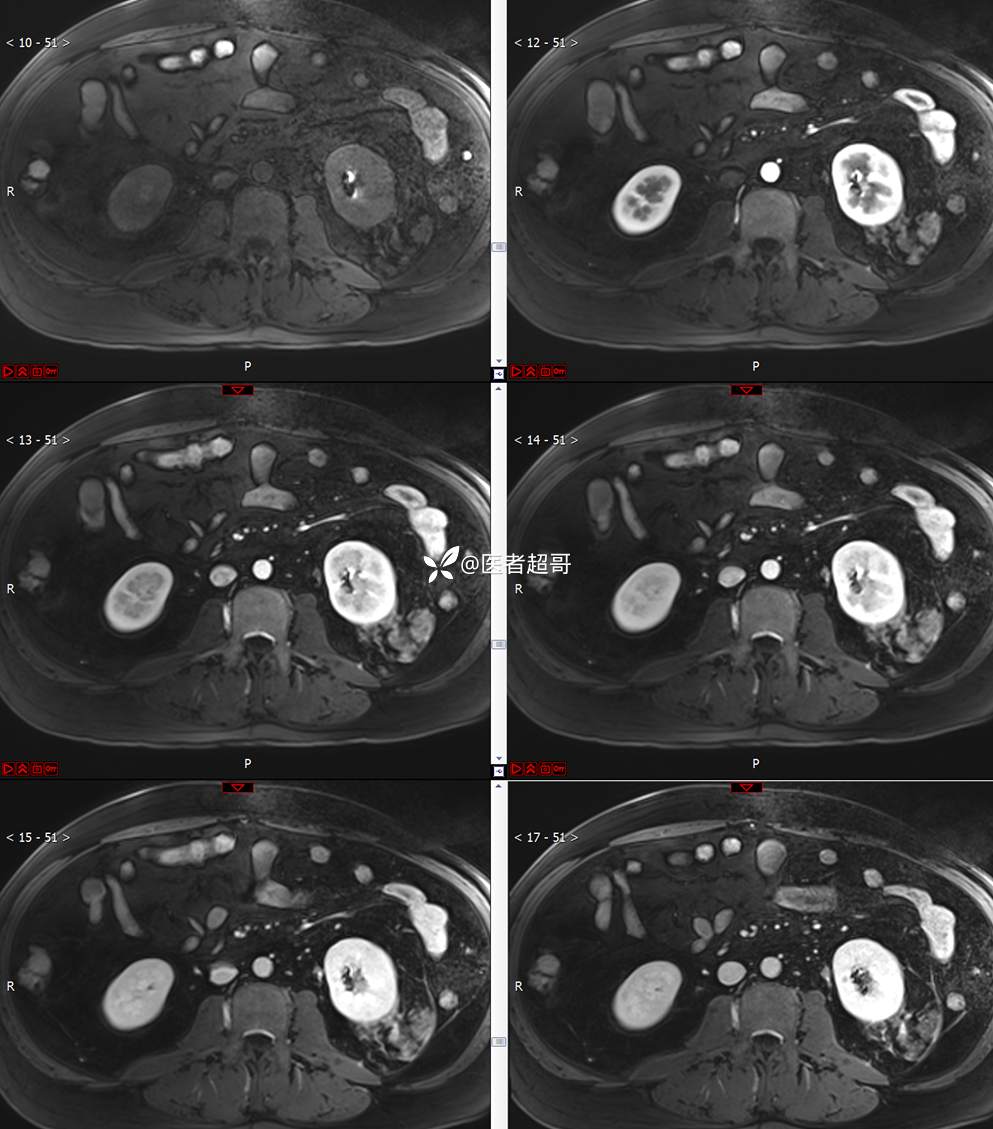

主 诉:查体发现左肾肿物9天。

现病史:患者9天前于附属医院行常规腹部CT检查时,发现左肾占位性病变并肾周脂间隙软组织增多,自述无明显腰腹部不适,无尿频、尿急、尿痛及肉眼血尿,未予特殊治疗,患者近期无头晕头迷,胸闷气急,腹胀腹泻及其他部位明显不适,遂至我院就诊,门诊以“肾肿物”收入院,患者自发病以来,精神可,睡眠饮食可,大便正常,体重无明显减轻。